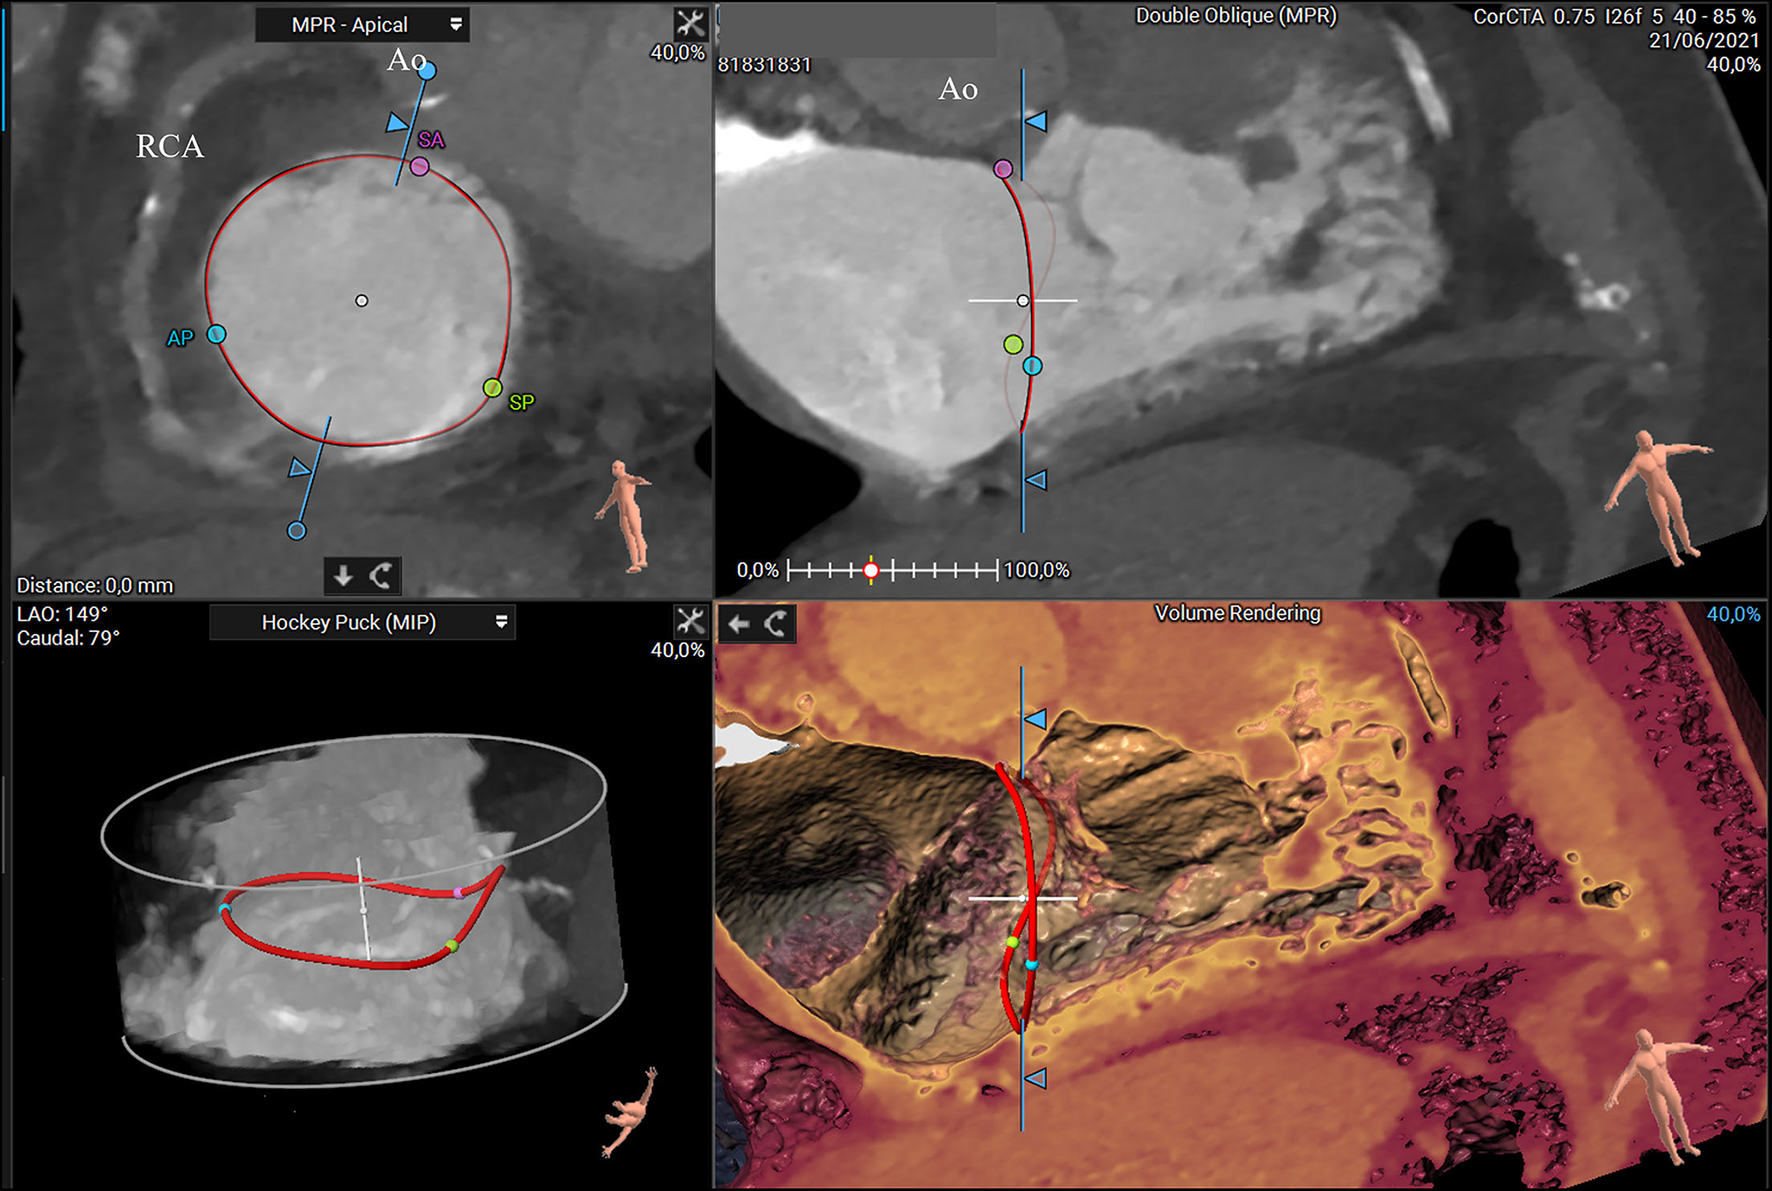

Figure 4

CTassessment of the tricuspid annulus using a semiautomated software-based approach (3mensio Structural Heart; Pie Medical Imaging, Maastricht, The Netherlands). Annulus and commissures are identified in end-systole in 2D and 3D view. The 3D reconstruction of the tricuspid annulus shows a non-planar structure saddle-shaped with two high points (anteroseptal and post-erolateral segments) and two low points (anterolateral and post-eroseptal segments). Ao, aorta; AP, anteroposterior commissure; RCA, right coronary artery; SA, septal-anterior commissure; SP, septal-posterior commissure.

Once the annulus has been manually or automated traced, commissures can be located, taking into account their unique anatomical findings. The fan-shaped chords can help in commissural identifications. Precisely, the AS commissure is placed anteriorly, just below the first right coronary tract and the anterior aortic valve cusp. At this site, it is possible to observe a short fan-shaped chorda, arising directly from the septal band of the crista supraventricularis or from a small papillary muscle on that band (8). The PS commissure is placed posteriorly after where the coronary sinus enters the atrium. Anatomically, it has three landmarks: a fan-shaped chorda, a papillary muscle, and a fold in the septal leaflet (8). The AP commissure is placed in correspondence of the free RV wall, usually below the right coronary artery (RCA), roughly at the acute margin. It is well-identified by a fan-shaped chorda and the anterior papillary muscle, which points toward this commissure. Once identified, distances between commissures and distances between the centrum of the TV and commissures can be measured.